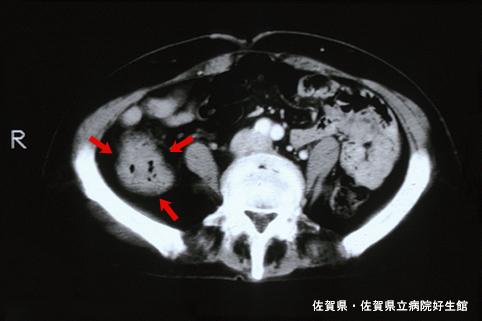

疾病(病理主体)的分类炎症性・溃疡性疾患/静脉硬化性大肠炎

部位(按器官分)大肠/升结肠

检查方法CT

肿瘤最大直径40以上